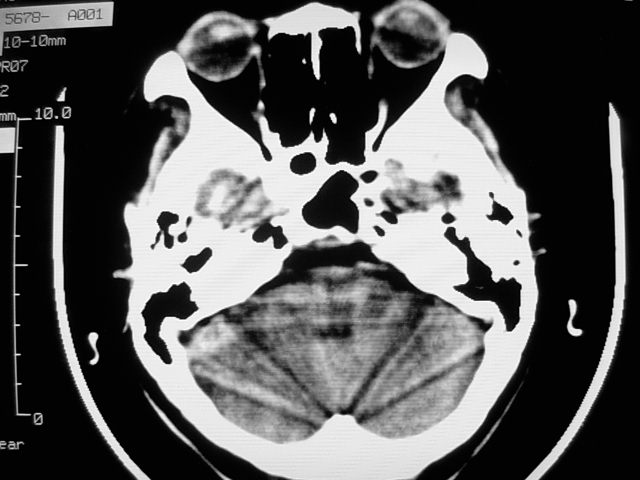

f39y,头疼、眩晕。患者拒绝强化。

左侧脑室增大,前角明显,中线向右移位,左侧脑室内见一肿块,密度不均,1室管膜瘤?2脑囊虫?

左额叶见一巨大椭圆形略低、低密度混杂密度肿块,边界清楚,似与侧脑室额角相通,明显占位效应,左侧侧脑室受压变形,右侧侧脑室扩大,中线结构向右明显弧形移位。鞍上池闭塞。

左侧脑室增大,前角明显,中线向右移位,左侧脑室内见一肿块,密度不均,内见钙化,1室管膜瘤?2脑囊虫?

类圆形低密度病灶与脑室内密度明显有差别,考虑:低密度病灶压迫四脑室形成的特殊影像。支持:皮样囊肿。